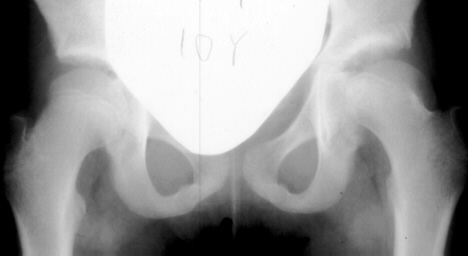

A ten year old female presented with a left hip dislocation. She was born by Cesarean-section because of slow progression of labor. The child was not breech and was noted to have a dislocatable hip at birth. There was a negative family history of DDH. An X-ray prior to application of the brace showed the dislocation of the hip. The patient was first seen at AIDI on 9th day. Abduction of the right hip was 80 degrees but left was only 60 degrees. There was a positive Galeazzi sign with the left hip being shorter than the right. X-rays showed a left hip dislocation and right hip subluxation . A Pavlik harness was applied. After two months, the right hip improved but the left hip was still dislocatable. For this, home traction was started. Even after 2 months, the left hip did not reduce. Therefore, an arthrogram, adductor tenotomy and closed reduction was done at 4 months of age. Single hip spica was applied with the hip in 40 abduction and 100 flexion. Eight weeks later an arthrogram was performed and the cast was reapplied with the hip in 35 degrees abduction and 100 degrees flexion.

Four months later, the spica cast was removed and an Atlanta brace was applied. X-rays showed avascular necrosis at ten months of age . At two years of age, the ossification of the left nucleus was still delayed. The leg lengths were equal and the range of motion of the hip was full.

The progression of the hip is documented by x-rays taken at 1 year of age, 2 years of age, 3 years of

age, 5 years of age, 7 years of age, then at ten years of age, early closure of the lateral portion of proximal growth plate observed. Coxa valga was also observed.